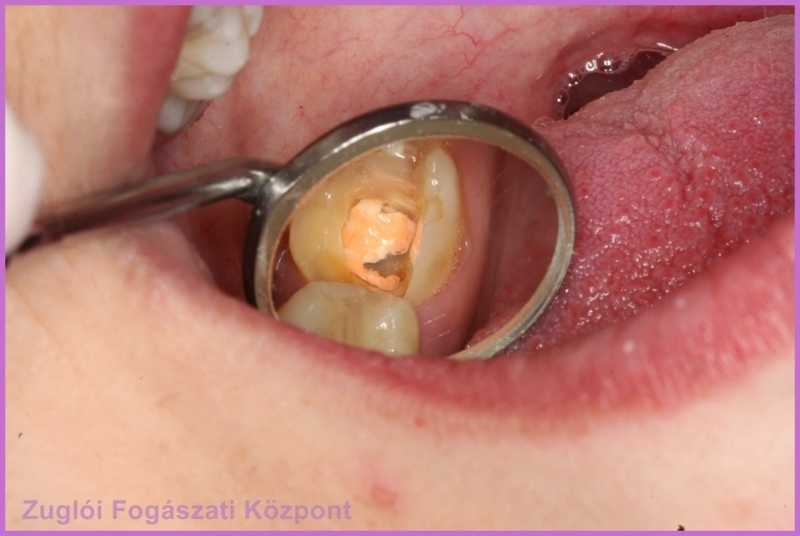

Csinos nőpáciensünk azzal a panasszal érkezett fogászatunkra, hogy egyik fogából letörött egy darab.

Dr. Holló Ádám, a rögzített és kombinált fogpótlások specialistája egy szájüregi vizsgálat után igazolta ezt a tényt, valamint azt, hogy a fogban levő gyökértömés inkomplett.

szájüregi vizsgálat